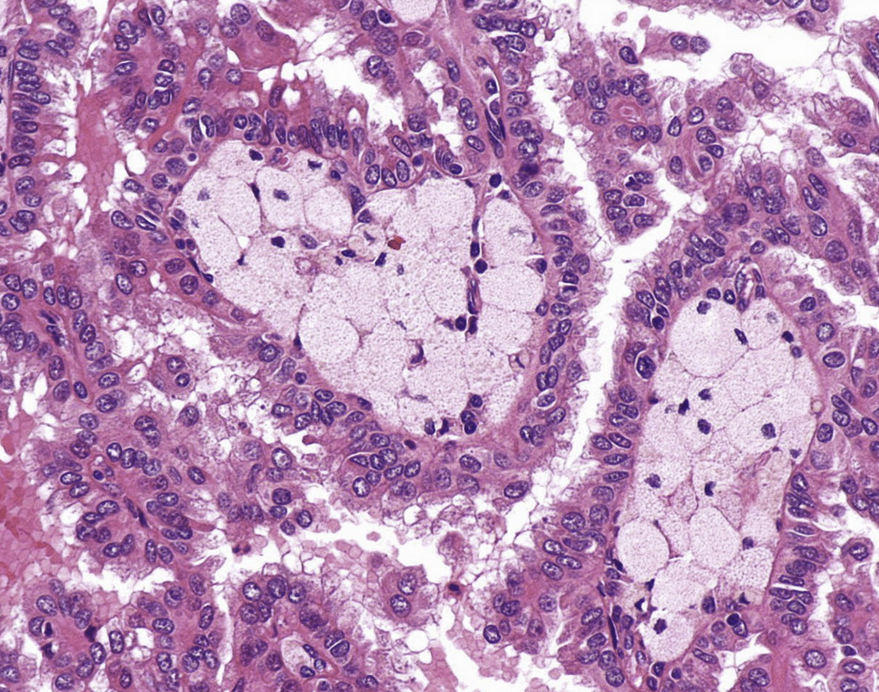

• most commonly consists of clear cells from the PCT

• less commonly arise from papillary tumors from the PCT or intercalated cell tumors (oncocytomas) associated with tuberous sclerosis